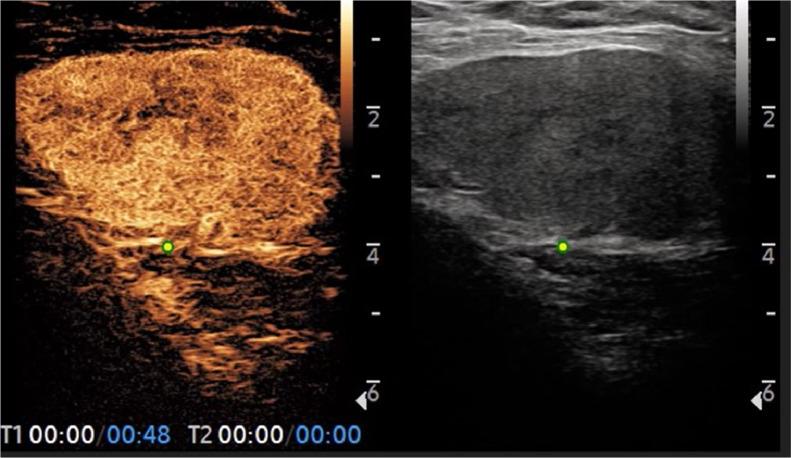

Haemangiomas have been described in many anatomic locations, but occur quite rarely in the breast; although unfrequent, they are the most common benign vascular tumors of the breast. They are comprised in the cathegory of mesenchymal lesions, a spectrum of lesions that arise in the stroma of the breast as defined by WHO. Here we present the case of a breast haemangioma in a 40-years-old woman, with history of a palpable lump in the left breast slowly increasing in size over time. The lesion first underwent diagnostic biopsy in 2018; after a 5-years follow-up with conventional ultrasound, it was studied in 2023 by our group using Contrast Enhanced Ultra-Sound (CEUS) in order to evaluate its vascularization. Basing on our experience, we conclude that in carefully selected cases of histologically proven breast haemangioma, a conservative management with follow-up imaging is safe; CEUS represents a noninvasive method for studying haemangiomas, superior than traditional US thanks to its ability to provide information about vascularity. In those cases with atypical imaging or clinical pathological suspicious characteristics, a complete surgical resection of the vascular tumor is mandatory-in order to exclude the possibility of an underlying angiosarcoma, especially when the lesion measures more than 2 cm.

血管瘤在许多解剖部位均有报道,但在乳腺中极为罕见;尽管不常见,但它们是乳腺最常见的良性血管肿瘤。它们属于间充质病变范畴,是世界卫生组织定义的一类起源于乳腺间质的病变。在此,我们报告一例40岁女性乳腺血管瘤病例,该患者有左乳可触及肿块病史,肿块大小随时间缓慢增大。该病变于2018年首次接受诊断性活检;在进行了5年的传统超声随访后,我们团队于2023年使用对比增强超声(CEUS)对其进行研究,以评估其血管化情况。根据我们的经验,我们得出结论,在经过精心挑选的组织学确诊的乳腺血管瘤病例中,采用随访成像的保守治疗是安全的;CEUS是一种研究血管瘤的非侵入性方法,由于其能够提供有关血管的信息,优于传统超声。在那些具有非典型影像学表现或临床病理可疑特征的病例中,必须对血管肿瘤进行完整的手术切除,以排除潜在血管肉瘤的可能性,尤其是当病变直径超过2 cm时。